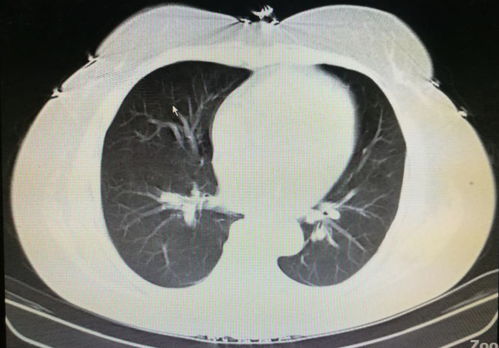

有一种特殊类型副肿瘤性天疱疮(PNP),它与肿瘤的关系更为密切。约9%-25%的PNP患者合并恶性肿瘤,这些肿瘤尤其是淋巴系统肿瘤和胸腺瘤等。PNP患者的血清中特定抗体的检测可以作为判断肿瘤存在的辅助指标。PNP的病情较为严重,常常伴随着闭塞性细支气管炎等并发症,其预后情况也相对较差。

预后情况对于合并肿瘤的天疱疮患者来说并不乐观,尤其是那些PNP伴随呼吸系统并发症的患者。天疱疮患者需进行定期随访,密切注意临床症状和实验室检查结果,以期早期发现潜在肿瘤,及时采取治疗措施。